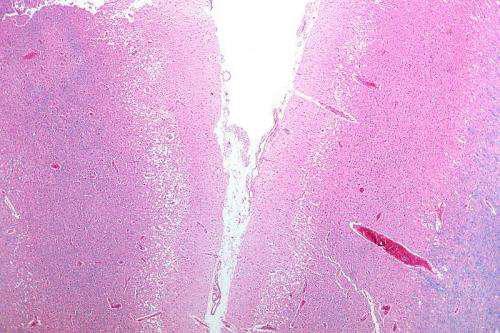

为了探究这些问题,他们在老鼠中引起了中风,损害了动物的运动能力,并发现LFOs减少了。在能够恢复的老鼠中,逐渐做出更快更精确的动作,LFOs也回来了。功能恢复与LFOs的再次出现有很强的相关性。完全恢复的动物比部分恢复的动物有更强的低频活动,而那些没有恢复的动物几乎没有低频活动。

为了促进恢复,研究人员使用电极记录活动,并向大鼠的大脑传递一种轻微的电流,刺激中风中心附近的区域。这种刺激持续增强了受损区域的LFOs蛋白,并似乎改善了运动功能:当研究人员在大鼠运动之前发出一阵电流时,大鼠伸手去抓食物小球的准确率高达60%。